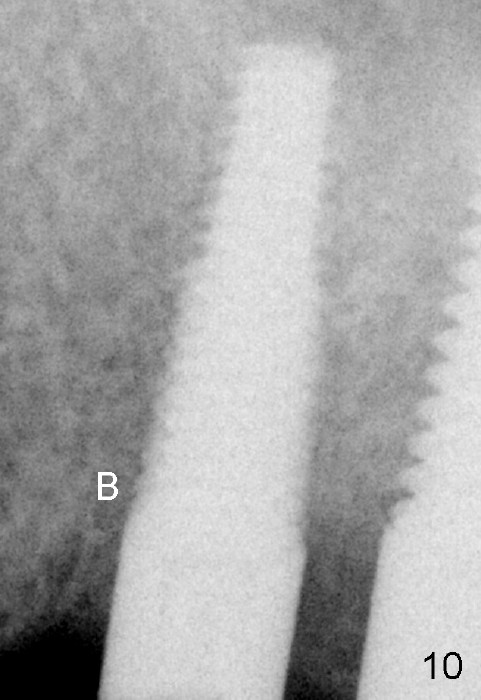

Fig.10: No matter where the bone comes from (Fig.7), the mesiobuccal socket is almost completely obliterated by bone growth (B) in 3.5 months postop.